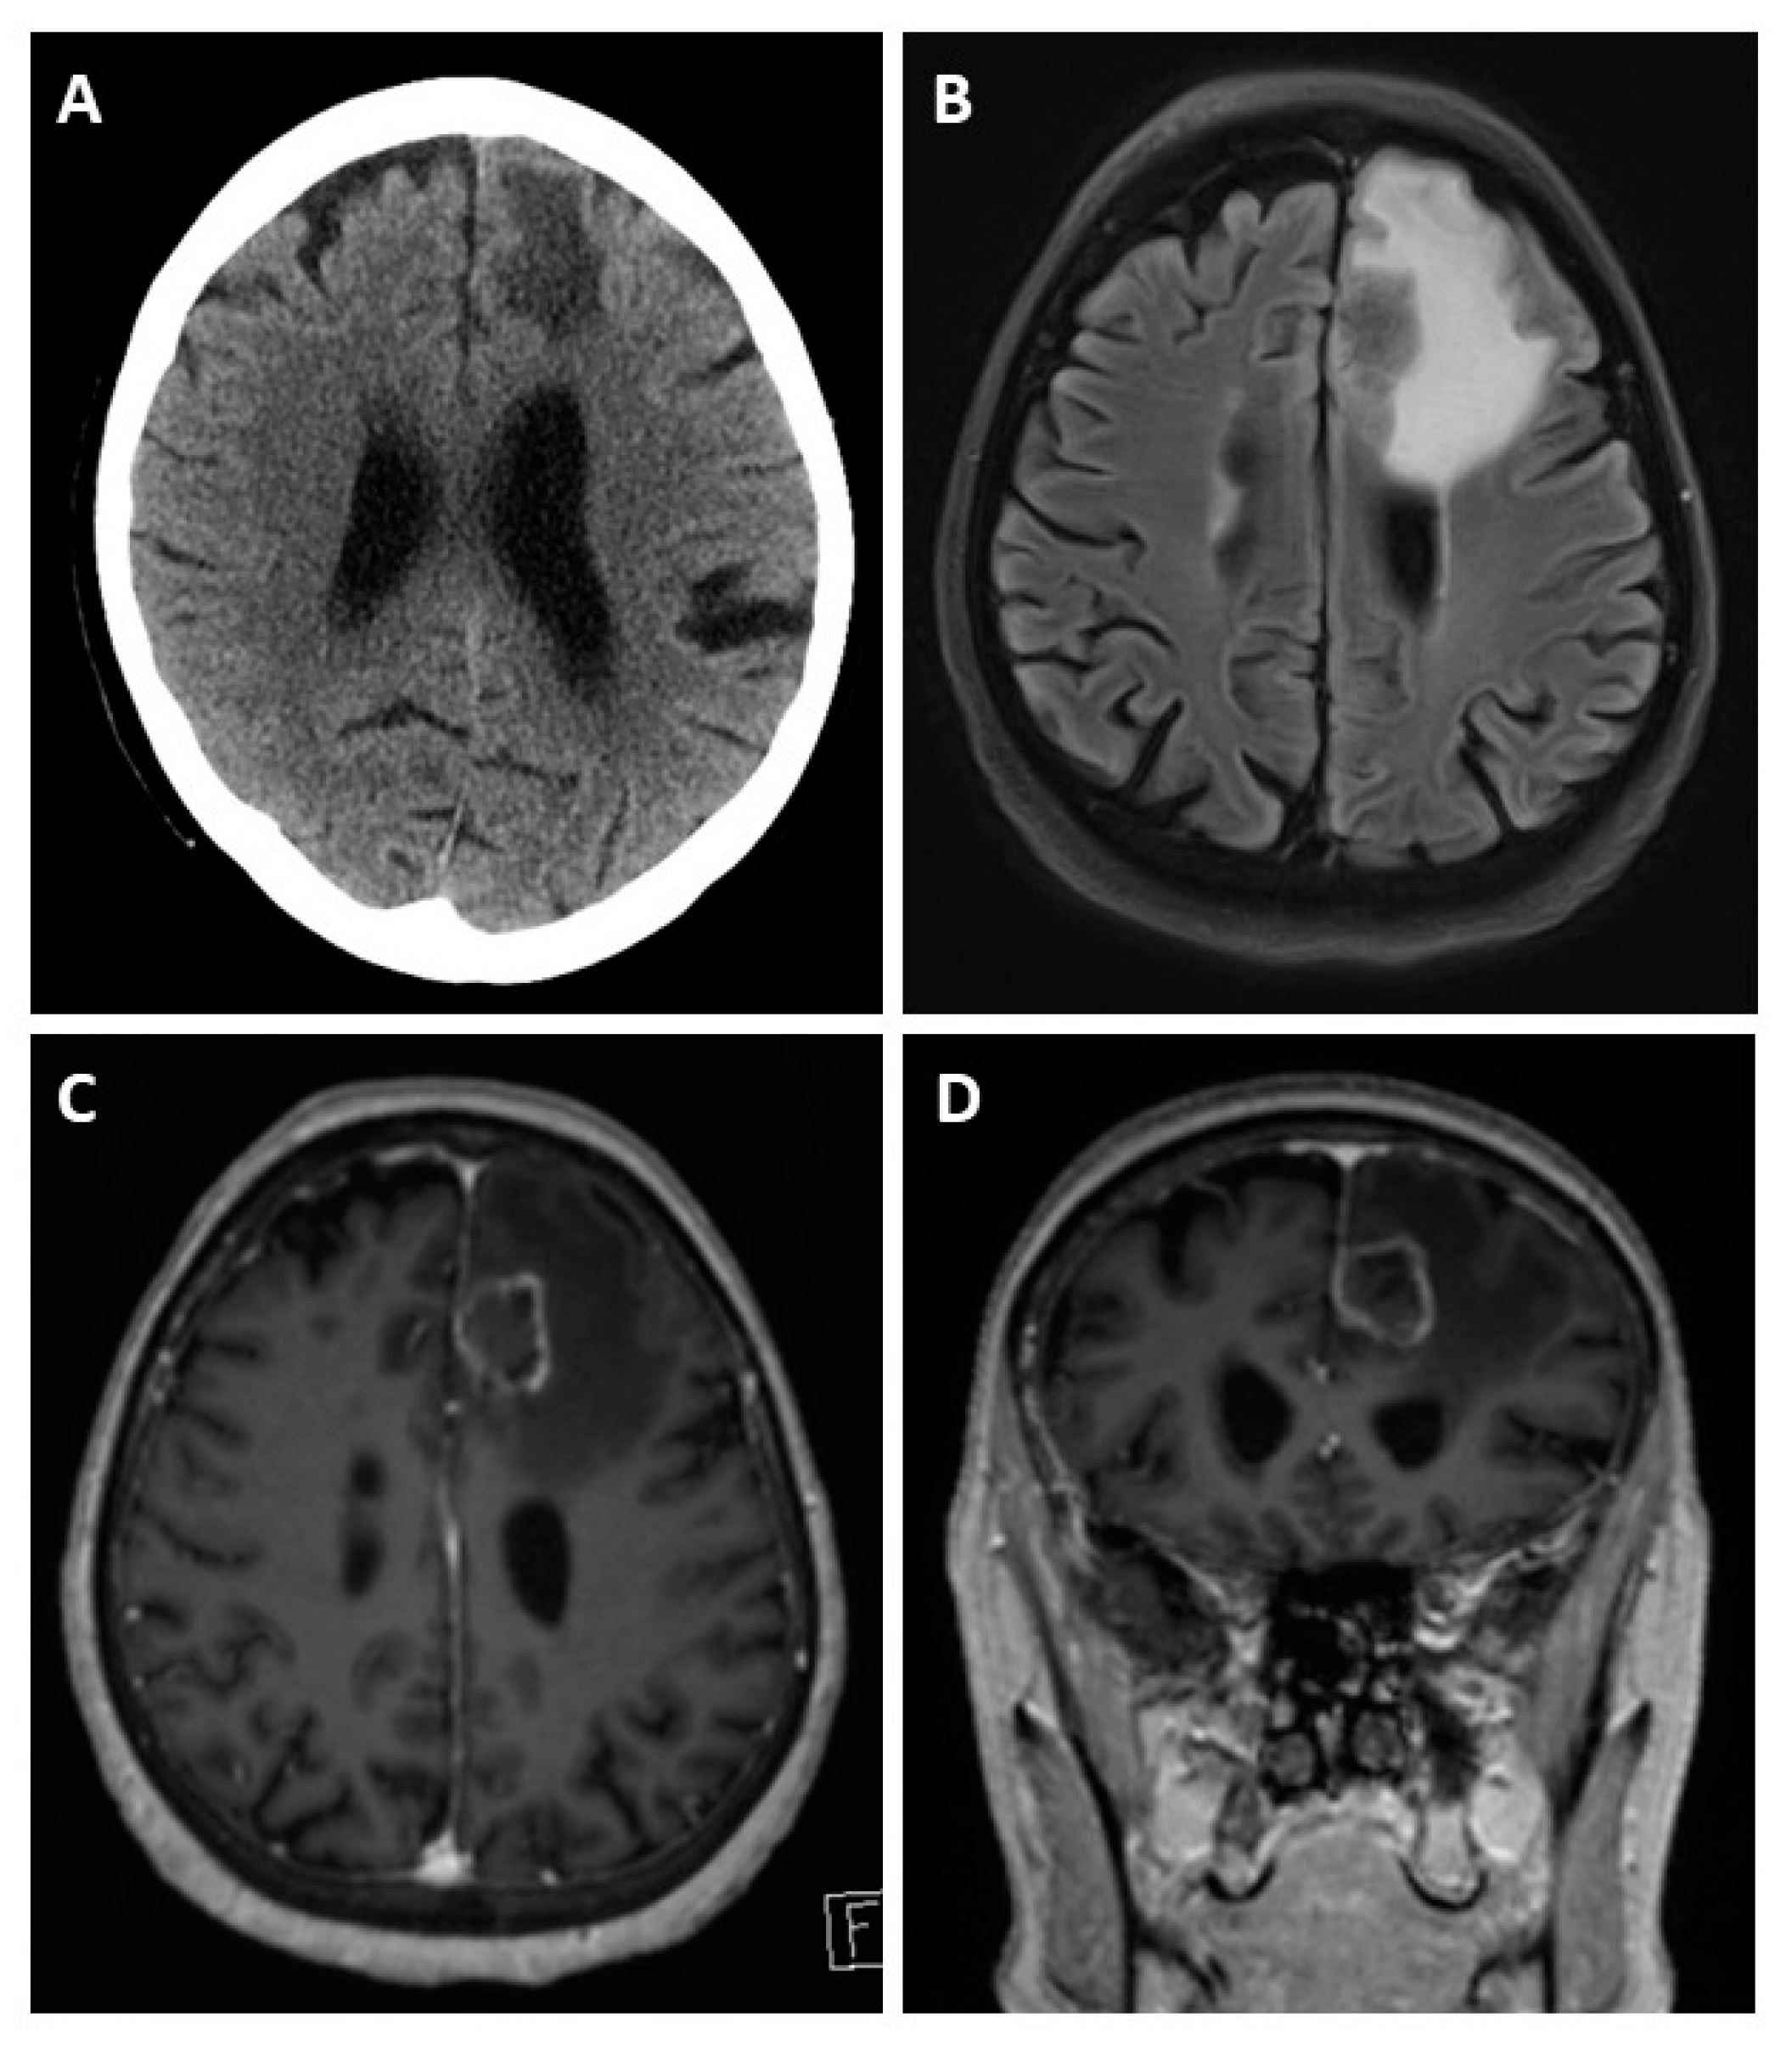

Figure 3.

Cerebral CT and MRI scans of a patient with BM, a 62-year-old patient presenting with left frontal edema in computed tomography (A). The MRI scan reveals the actual extent of the edema in the fluid-attenuated inversion recovery (FLAIR) sequence (B). T1-weighted gadolinium post-contrast images in the axial (C) and coronal (D) orientation reveal causative left-frontal CRC metastasis.